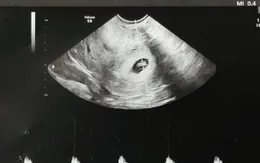

Lần đầu tiên ghi lại quá trình cấy ghép phôi người vào tử cung

VTV.vn - Đoạn phim 3D lần đầu cho thấy phôi người cấy vào tử cung, mở ra hy vọng cải thiện điều trị vô sinh.